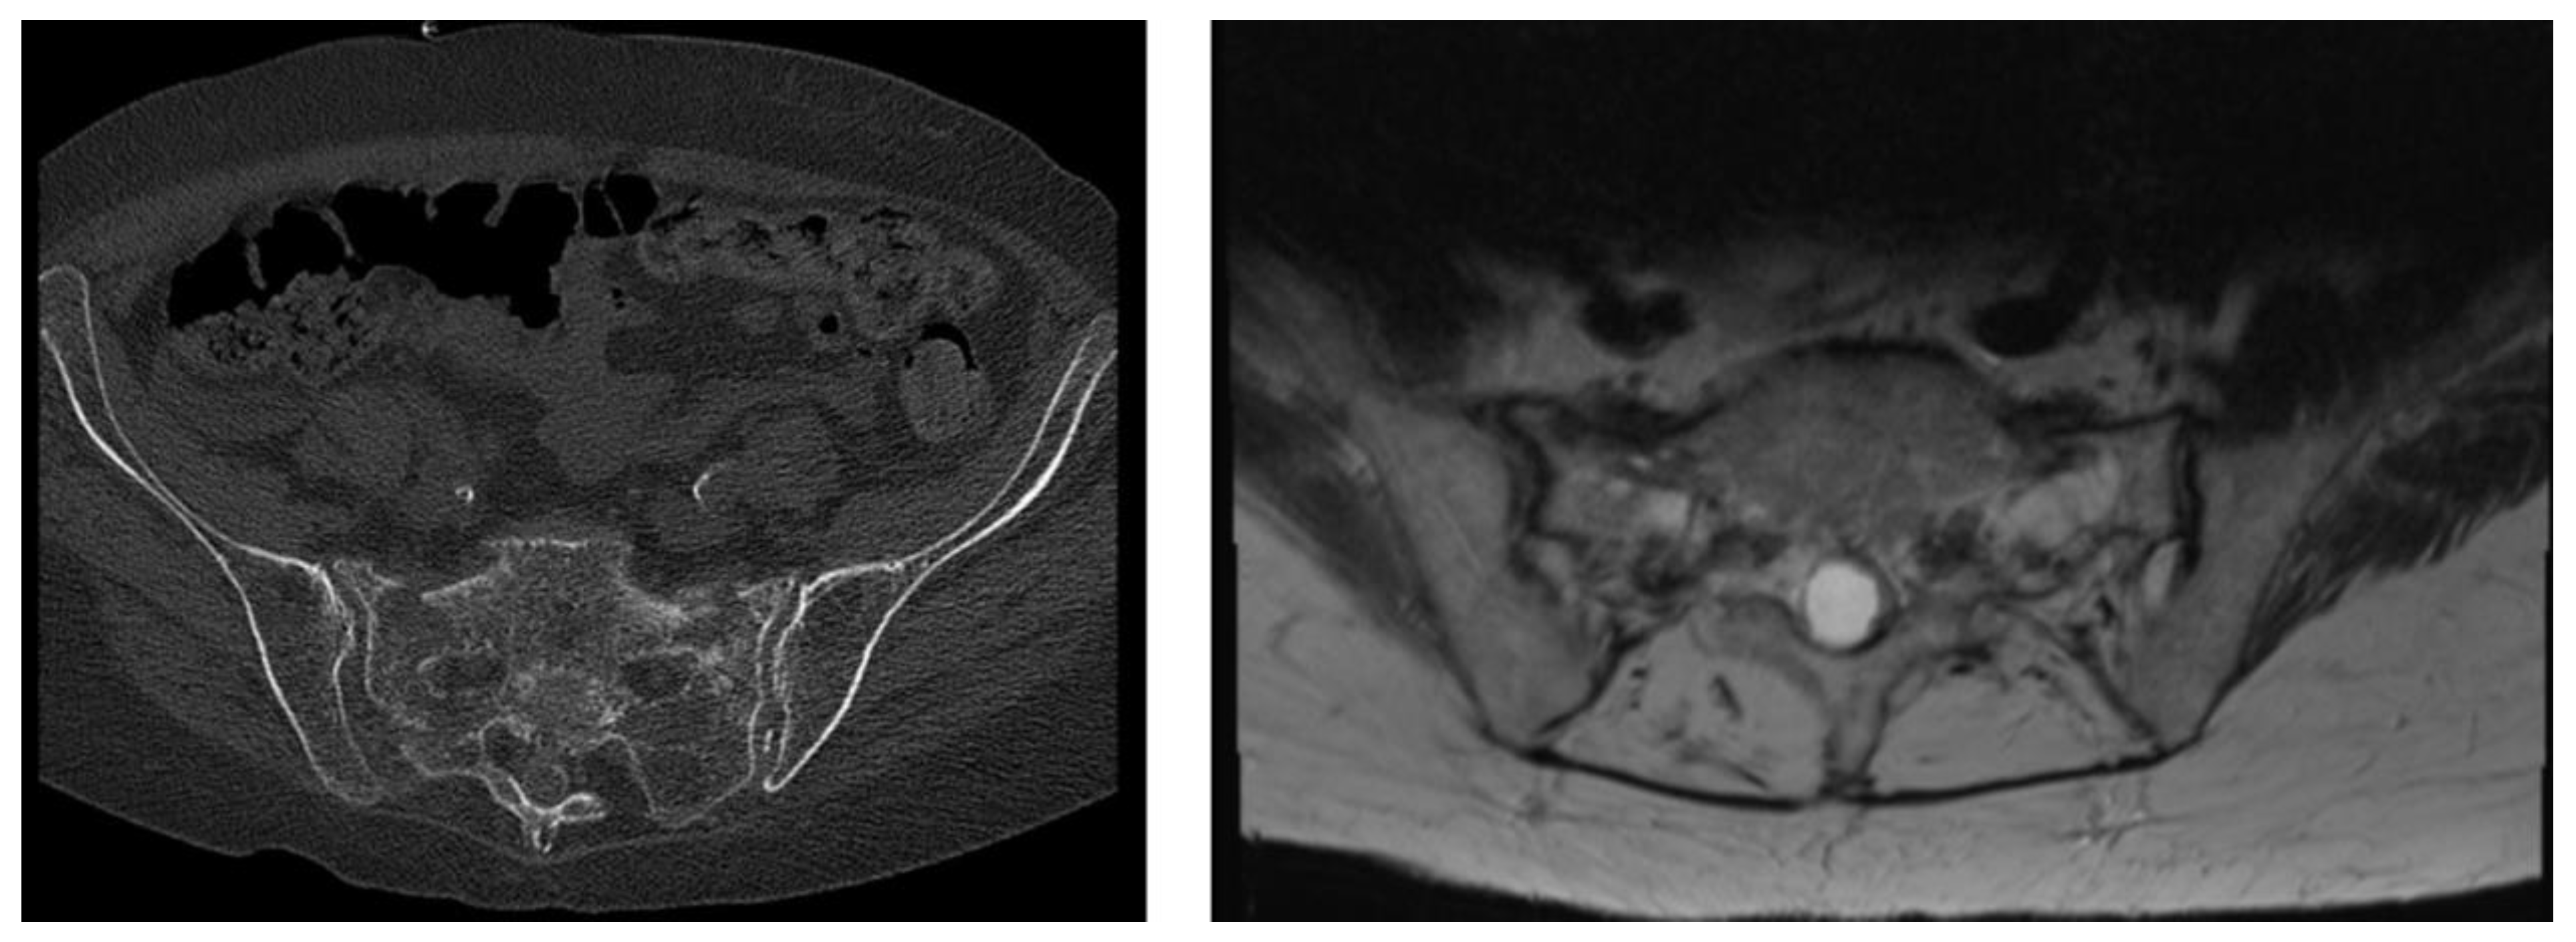

3.2. Distribution of FFP Types According to the FFP Classification System [9] and OF-Pelvis Classification System [10]

3.3. Spinopelvic Parameters